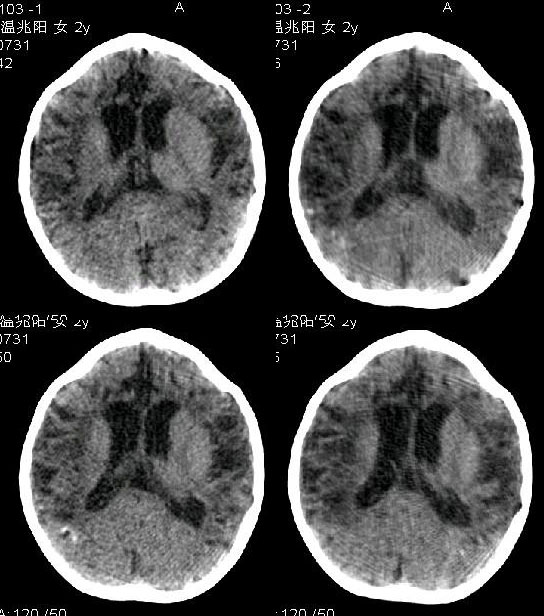

本例特点:1 脑室扩大.以三脑室,四脑室扩大为主.2 脑沟 脑裂增宽,以纵裂增宽为主.3 脑实质内大量低密度影,(提示缺血及脱髓鞘变性).4 双侧顶枕部点状钙化.

结合临床考虑:1 神经皮肤综合征_结节性硬化.2 胼胝体发育不良.

诊断:1脑发育不良,2脑炎性病变可能。3建议mri检查

脑小畸形

我觉得像是:脑炎后遗症。